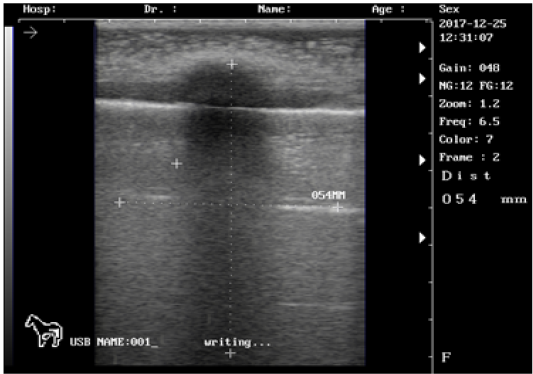

Ultrasound images of the testis of 4 months lamb showing: moderate echogenicity of the testicular parenchyma; mediastinum testicular highly echogenic